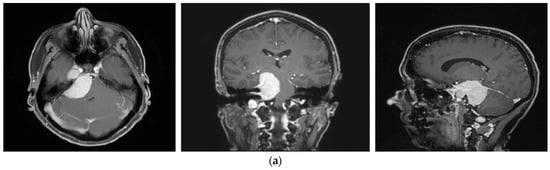

A 58-year-old female presented with progressive headache, difficulty swallowing, diplopia, hearing loss, and reduced face sensitivity on the right side (Figure 4). Elective craniotomy and AHSA-assisted tumor resection were performed. The patient underwent hypofractionated radiosurgery (5 × 5 Gy) of the residual meningioma one year after tumor resection.

Figure 4.

Second representative case of AHSA-supported tumor resection. (a) MRI imaging of petroclival meningioma (axial, coronal, sagittal). (b) Depiction of preoperative tumor volume (orange) and planned residual tumor volume (red). (c) AHSA summary table showing the stereotactic radiation constraints for the preoperatively planned residual tumor volume. With this plan, conventional fractionation and hypofractionation were feasible with effective tumor coverage.

—right optic tract: mean dose unsafe, max. dose safe. (i) Comparison of pre- and 3 months postoperative MRI for stereotactic radiation planning. The residual tumor was finally treated with hypofractionated radiotherapy (5 × 5 Gy).